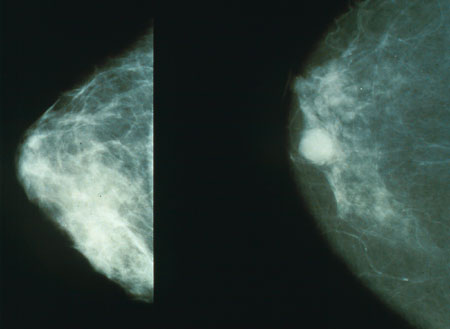

৫০ থেকে ৭০ বছর বয়সী নারীদের প্রতি তিনবছর পর পর ব্রেস্ট স্ক্রিনিং বা ম্যামোগ্রাম করানো উচিত। ম্যামোগ্রাম হচ্ছে এক্সরের মাধ্যমে নারীদের স্তনের অবস্থা পরীক্ষা করা। সাধারণত প্রাথমিক অবস্থায় ক্যান্সার এতো ছোট থাকে যে বাইরে থেকে সেটা বোঝা সম্ভব হয় না। কিন্তু ম্যামোগ্রামের মাধ্যমে খুব ছোট থাকা অবস্থাতেই বা প্রাথমিক পর্যায়েই ক্যান্সার নির্ণয় করা যায়। প্রাথমিক পর্যায়ে ধরা পরলে ক্যান্সার থেকে সুস্থ্য হয়ে ওঠার সম্ভাবনা প্রচুর থাকে। আর এই পরীক্ষার জন্য মাত্র কয়েক মিনিট সময় লাগে।বিআরসিএ অথবা ব্র্যাকা নামের একটি জিন আছে সবার শরীরে। কিন্তু এই জিনের কোনও একটিতে যখন ত্রুটি দেখা দেয় তখন সেটা ডিএনএর ক্ষতি করতে পারে এবং তার জের ধরে শরীরের কোষে ক্যান্সারও দেখা দিতে পারে।যুক্তরাজ্যে স্তন ক্যান্সারের যত রোগী আছেন তাদের প্রায় ৫ শতাংশের শরীরেই আছে এই ব্র্যাকার ত্রুটিপূর্ণ জিন। আর এই জিনটিকে নির্মূল করতে অপারেশনের মাধ্যমে স্তন কেটে ফেলে দেওয়া হয় চিকিৎসা বিজ্ঞানের পরিভাষায় যাকে বলা হয় ম্যাসটেকটোমি।ব্রিটেনে সাউদাম্পটন বিশ্ববিদ্যালয়ের এক গবেষণায় বলা হয়েছে ত্রুটিপূর্ণ ব্র্যাকা জিন আছে স্তন ক্যান্সারের যেসব রোগীর শরীরে তাদের বেঁচে থাকার সম্ভাবনা আর যাদের শরীরে এই ত্রুটি নেই তাদের বেঁচে থাকার সম্ভাবনার সমান।প্রায় তিন হাজার রোগীর উপর এই গবেষণাটি চালিয়ে দেখা গেছে রেডিওথেরাপি কিম্বা ম্যাসটেকটোমি যে ধরনের চিকিৎসাই তারা নিয়ে থাকুক না কেনো তার ফলাফল একই দাঁড়ায়।বিশেষজ্ঞরা মতে এর অর্থ হলো স্তন কেটে ফেলে দেওয়ার মতো বড়ো রকমের এক সিদ্ধান্ত নেয়ার ক্ষেত্রে অল্প বয়সী নারীরা আসলে একটু সময় নিতে পারেন।বিআরসিএ বা ব্র্যাকার দুটো জিন আছে ব্র্যাকা এক এবং ব্র্যাকা দুই। চিকিৎসকরা বলছেন এই জিনের রূপান্তরের ফলে ক্যান্সারে আক্রান্ত হওয়ার ঝুঁকি চার থেকে আটগুণ বেড়ে যায়। যেসব নারীর উপর এই গবেষণাটি চালানো হয়েছে তাদের ১২ শতাংশের ক্ষেত্রেই দেখা গেছে যে তাদের শরীরে ব্র্যাকার রূপান্তর ঘটে সেখানে ত্রুটি দেখা দিয়েছিলো।চিকিৎসকদের গবেষণায় আরো দেখা যায় যেসব রোগীর শরীরে ব্র্যাকা ত্রুটি ছিলো এবং যাদের ছিলো না তারাও প্রায় একই সময়কাল পর্যন্ত বেঁচে ছিল।তবে গবেষকরা বলছেন নতুন করে দীর্ঘ মেয়াদী সময়ে যাতে ক্যান্সার হতে না পারে সেজন্যে রোগীদের শরীরে এই ম্যাসটেকটোমি উপকারী হতে পারে।